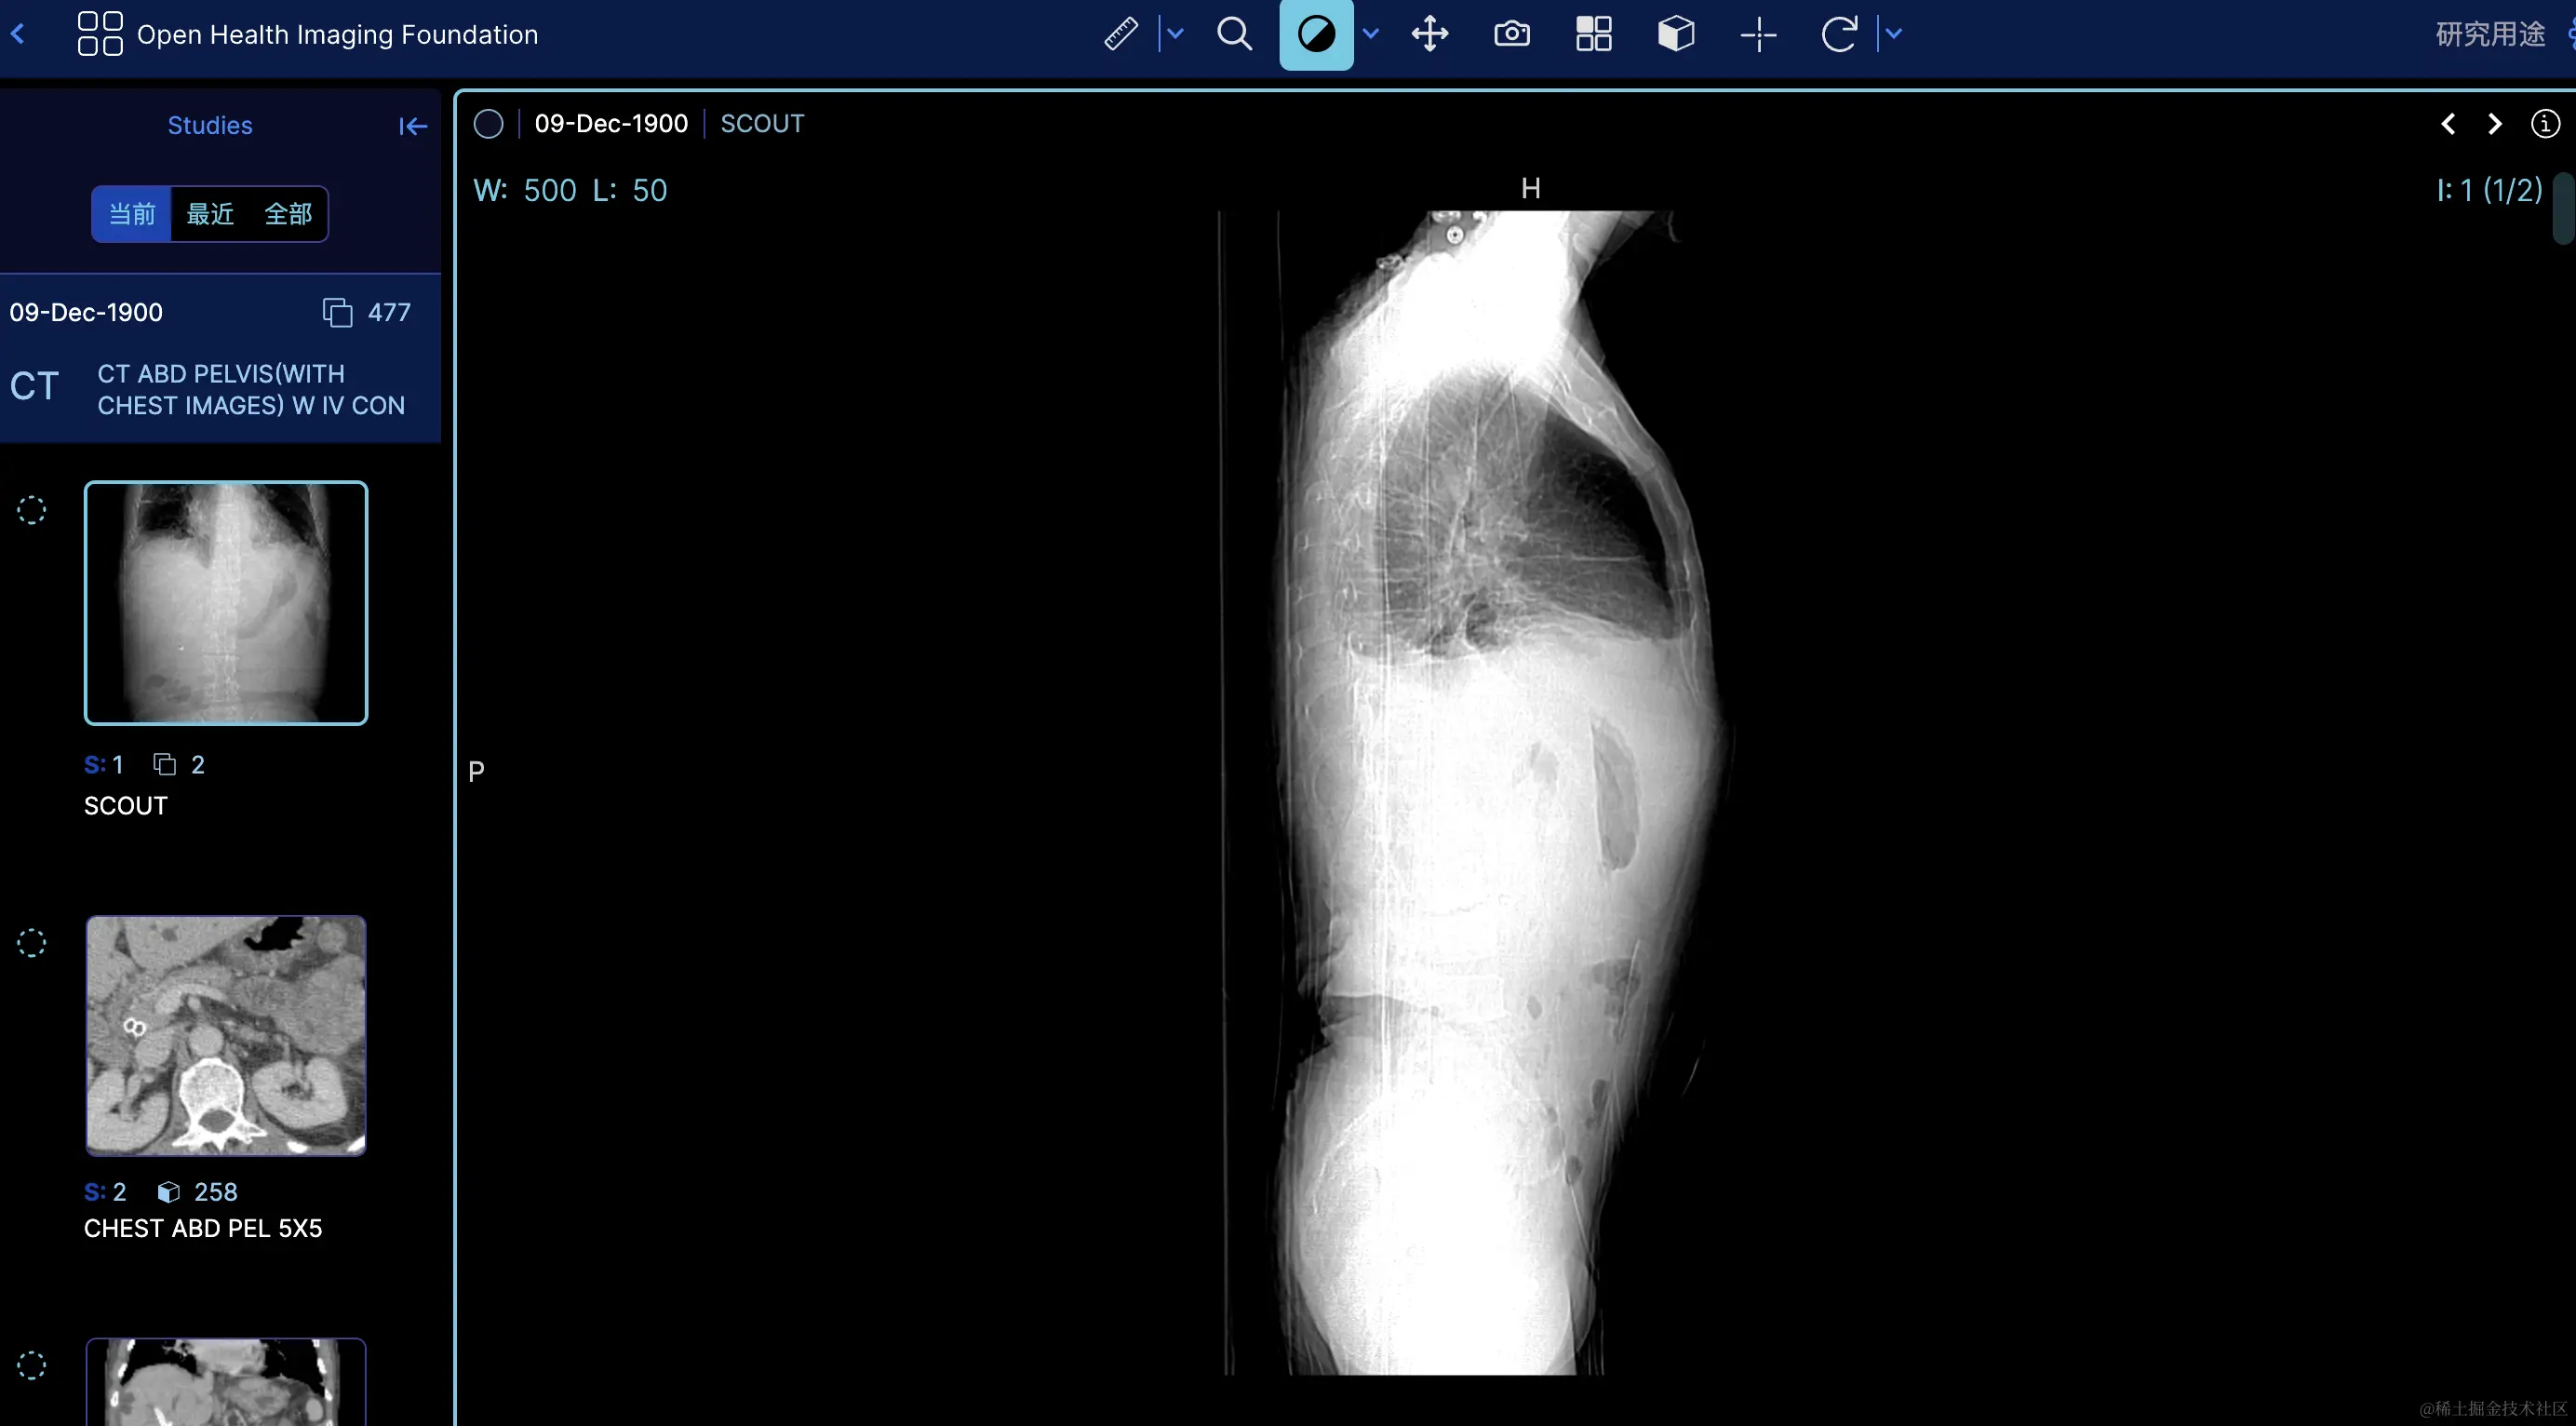

OHIF是一个开源的医学影像查看器,特别为Web环境设计,支持DICOM标准并且可以集成到现代的医疗影像处理流程中,提供了一个功能丰富的平台,使医疗专业人员能够查看、分享和分析医学影像。 image.png image.png